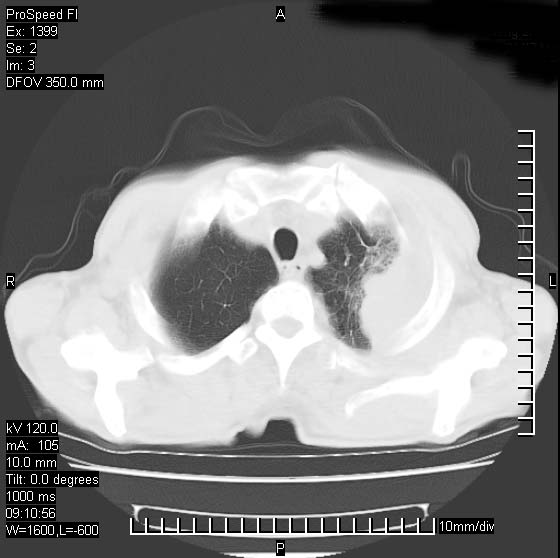

以下是引用卜一在2007-1-19 9:55:00的发言:[br]左肺沿胸膜下巨大肿块影,边缘呈分叶征,纵隔内见肿大淋巴结,右肺内另见一不规则结节影 .考虑:左肺周围性肺癌伴纵隔 右肺内转移.